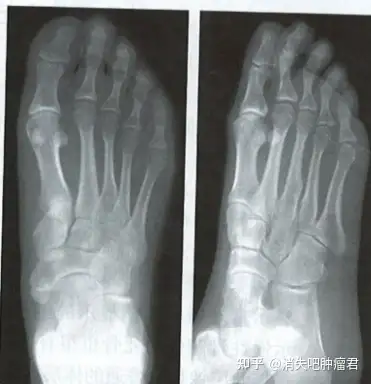

足部正侧位

右足正侧位x光片:右足第5跖骨头外侧骨赘形成,第4.

请教各位:右足正侧位片